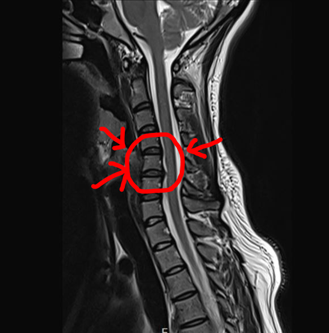

결과는 예상대로였어요. 경추 5-6번 디스크 돌출이 확인되었거든요.

사진에서도 보이시죠?

목뼈 사이에 있는 납작한 동그란 디스크가 튀어나와

기다란 척수를 누르고 있는 모습이요.

네 여기 말입니다 ^^